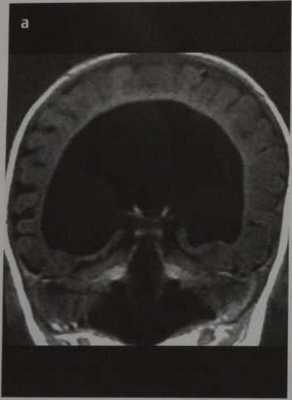

Семилобарная голопрозэнцефалия. МРТ, Т1 -ВИ во фронтальной плоскости. Визуализируются рудиментарные височные рога боковых желудочков, неполный гиппокамп, частично разделенные таламусы, отсутствие прозрачной перегородки.

Семилобарная голопрозэнцефалия:

- Продольная щель

- Имеются задние рудименты серпа большого мозга

- Лобный отдел мозга недоразвит и не разделен

- Таламусы частично разделены

- Рудиментарные височные рога боковых желудочков

- Неполный гиппокамп

- Отсутствует прозрачная перегородка

- Ствол мозолистого тела отсутствует; валик имеется.

б) При семилобарной голопрозэнцефалии межполушарную щель определяют между затылочными долями. Таламусы частично разделены, вследствие чего III желудочек небольшого размера. Лобные доли не разделены. Мозолистое тело не визуализируют.